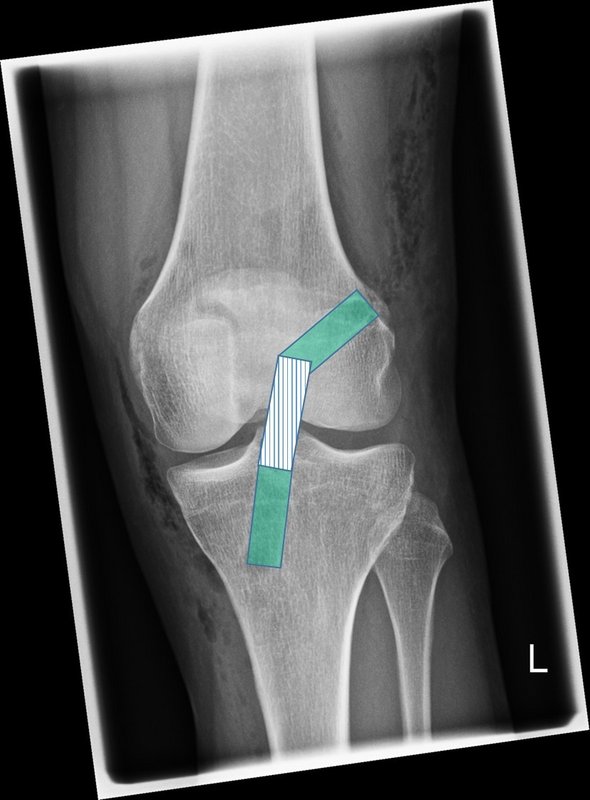

Beinachsfehlstellungen

Manchmal liegen Beschwerden Fehlstellungen zu Grunde – sei es im Sinne eines „O-Beins“ bzw. eines „X-Beins“, aber auch eine Rotationsfehlstellung kann ursächlich für Beschwerden des Kniegelenkes sein. Gerade bei Knorpelschädigungen und Arthrose ist eine Fehlstellung mit konsekutiver Überlastung einer Gelenkhälfte oftmals ursächlich. Durch den Ausgleich der Fehlstellung wird die Biomechanik des Gelenkes wieder hergestellt und das betroffene Areal entlastet. Wir bieten Umstellungen in allen Ebenen (O-Bein, X-Bein, Rotationsfehlstellungen, pathologischer Slope, …) an. Oft ist es sogar möglich, dass eine notwendige endoprothetische Versorgung nochmals lange hinausgezögert werden kann, was vor allem jungen Patienten zu Gute kommt.